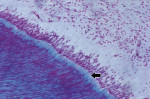

In the coronal portion, 100% of the samples presented loose connective tissue, with predominance of fibroblasts and few collagen fibers. The odontoblast layer at the periphery of the pulp connective tissue presented a palisade arrangement. The odontoblasts were separated from the mineralized dentin by predentin, which was shown as a layer of nonmineralized organic matrix indicative of odontoblastic activity (Figure 1), compatible with health.

In the radicular pulp, the histologic findings included: 1) pulp atrophy, characterized by the reduction in pulp space due to the formation of reparative dentin, with reduction in the number and size of cells (Figure 2); 2) reparative dentin, very irregular with little canalicular disposition; 3) an increase in the number and thickness of collagen fibers (fibrosis), disposed in a thick web oriented in the axial direction of the canal (Figure 2); 4) dystrophic calcification, observed along the entire extension of the canal (These findings were presented in the form of irregular and elongated amorphous structures, disposed along the rich network of collagen fiber bundles.) (Figure 3 and Figure 4); and 5) inflammatory infiltrate, which was present in the connective pulp in the apical region with predominance of chronic inflammatory cells.